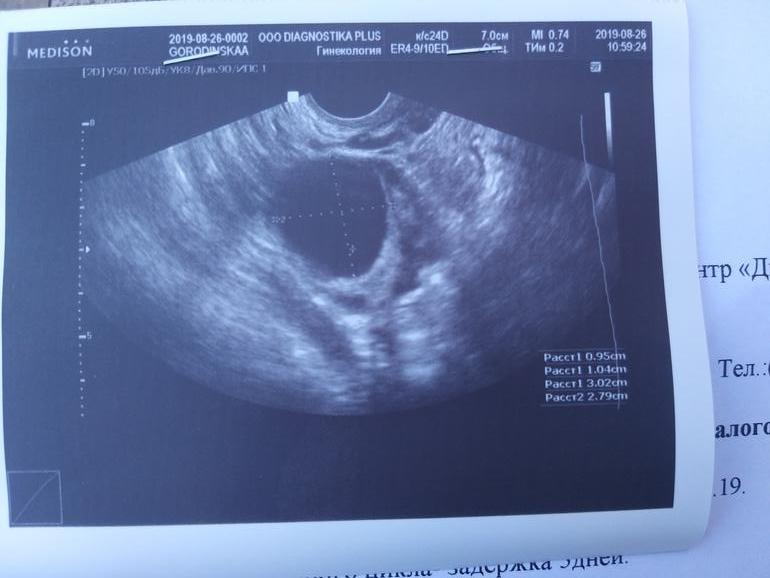

24.08 был наиположительнейший тест на овуляцию, 26.08 на УЗИ не нашли ЖТ, вместо него нашли фолликулярная кисту...